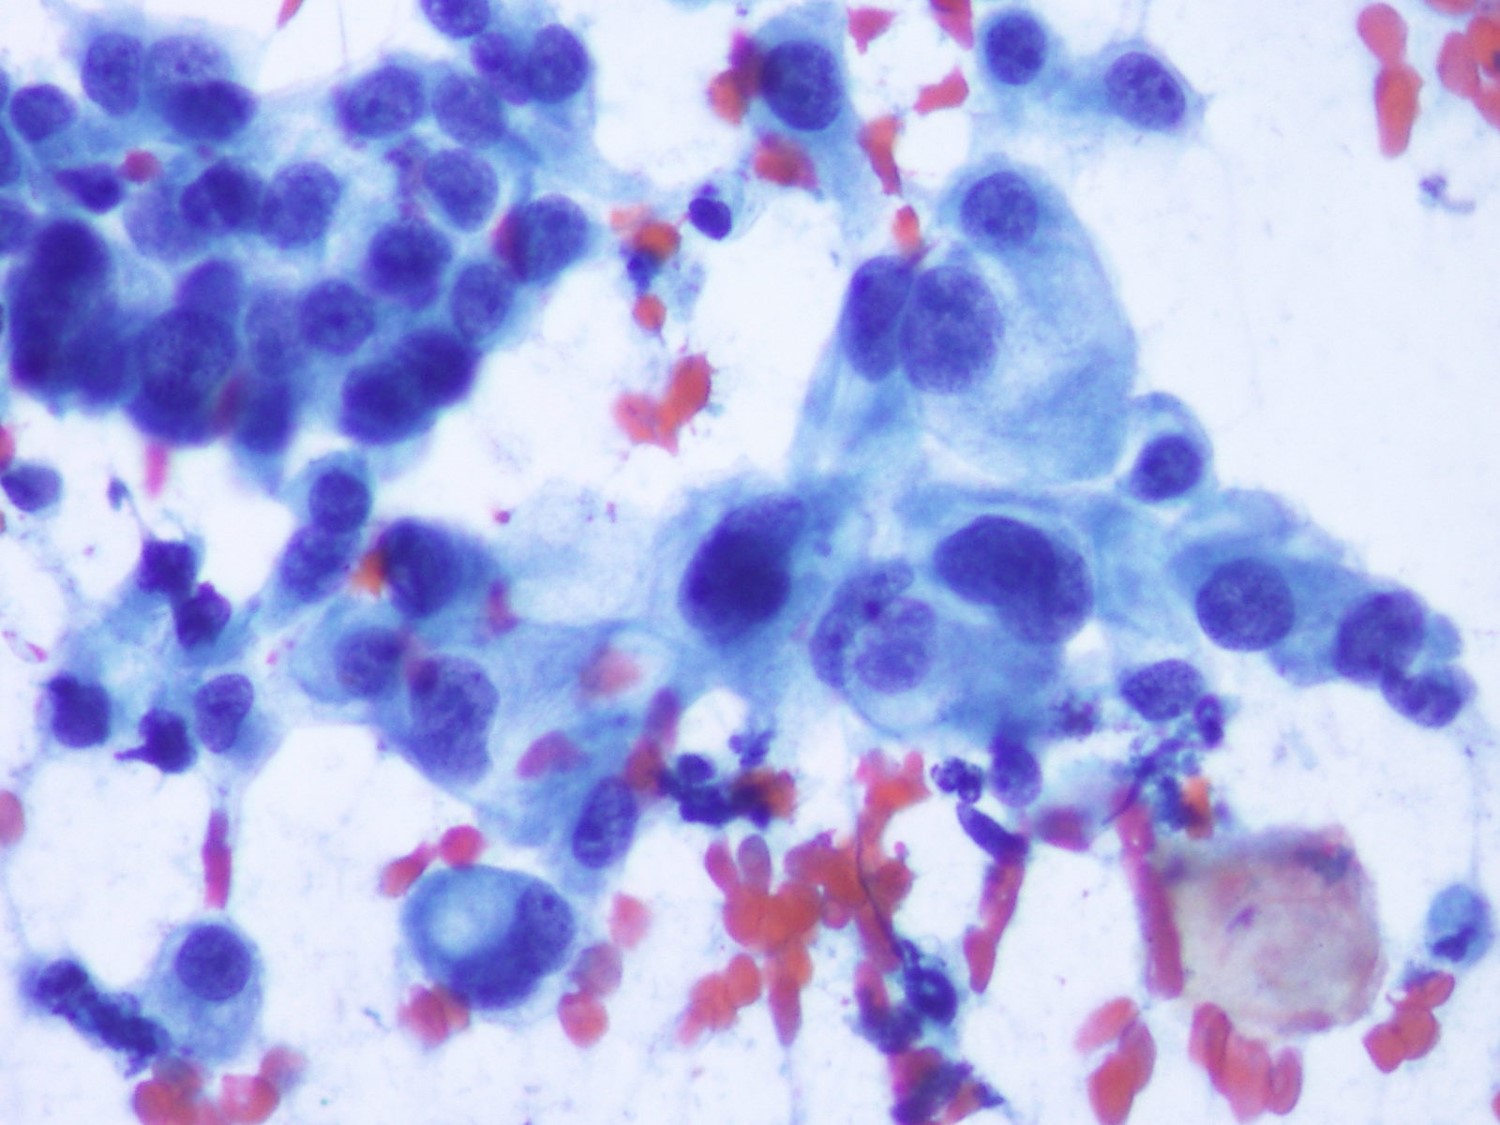

Hombre de 59 años, bronquítico crónico que refiere aumento del volumen mamario bilateral. Con una TC que informa masa tumoral en mediastino medio, voluminosa, sólido- quística, con extensa necrosis tumoral y adenopatías mediastínicas paratraqueales de tamaño significativo. Se realizar una PAAF guiada Ultrasonografía Ecobroncoscópica (EBUS) para el diagnóstico definitivo.

Dona de 77 anys amb lesió umbilical costrosa. Onfalitis crònica. No història de síndrome tòxica ni antecedents patològics importants. Es practica PAAF de la lesió umbilical. Posteriorment refereix discret augment del perímetre abdominal desde fa mesos. En la ECO abdominal: abundant quantitat de líquid ascític que es punciona obtenint 20 cc. de líquid serós.